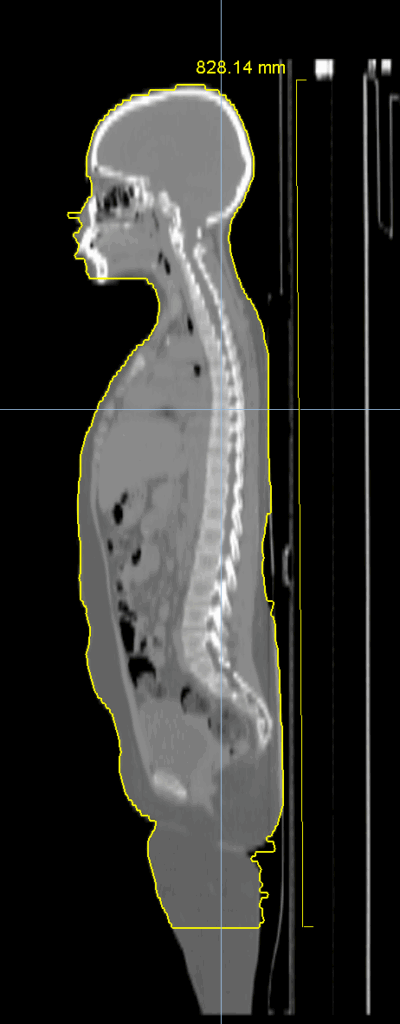

Planning CT Images

PTV(s) Volume, Length

27500 cc, 84 cm